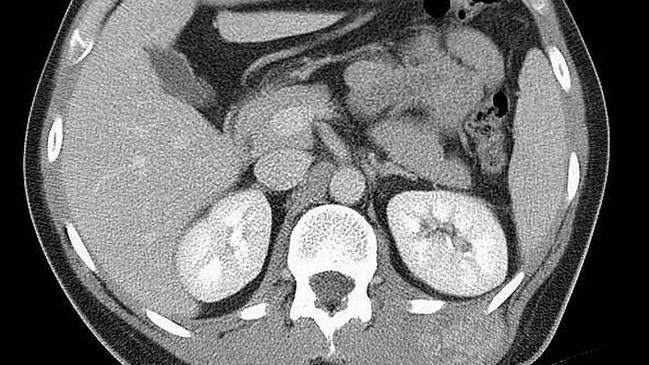

Widoczny guz w okolicy mięśni grzbietu, po stronie lewej.